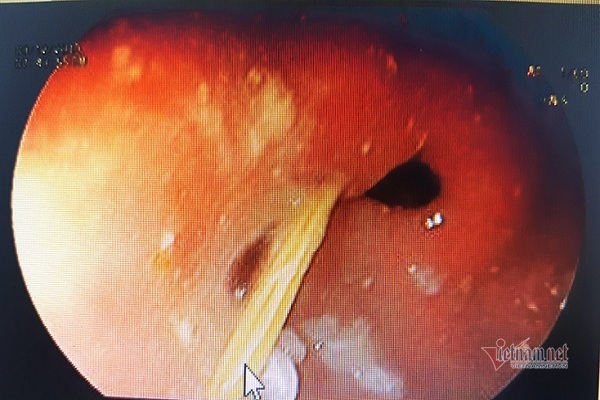

Bệnh viện Chợ Rẫy gắp con sán dài hơn 1m ra khỏi ruột bệnh nhân

Bệnh nhân (59 tuổi, ở Đồng Nai) cho biết có thói quen ăn bò tái. Khi chế biến thịt bò, ông chỉ vắt chanh hay chần thịt với nước nóng chứ không nấu chín kỹ.